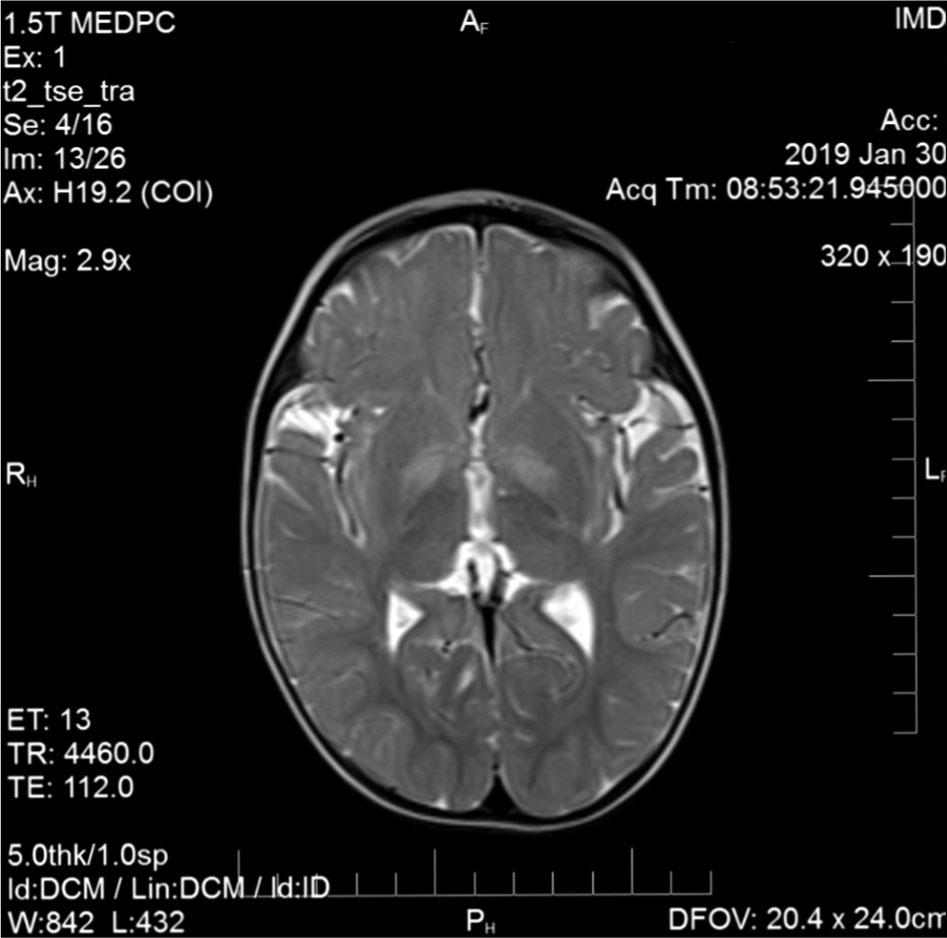

At eight months of age, a psychological assessment showed severe psychomotor developmental delay. The parents reported the absence of appropriate reactions to sound. Brain magnetic resonance imaging (MRI) showed incomplete myelination and high signal intensity in bilateral globi pallidi (figure 1). At the age of one year, brainstem evoked response audiometry (BERA) revealed a bilateral sensorineural hearing impairment, a “cookie bite” type audiogram was approximated (figure 2), and hearing aid was applied.

Brain MRI scan at the age of 15 months in a boy with SSADH deficiency revealing incomplete myelination and signal hyperintensity in globi pallidi

A diagnostic procedure which usually provides SSADH deficiency suspicion is the analysis of urinary organic acids. In SSADH deficiency patients, this test typically shows a multifold increase of GHB concentration. Failure to identify GHB in urine by the gas chromatography–mass spectrometry method in our patient could be attributed to inadequate sampling or other technical reasons for false negativity. However, repeated measurements in urine were performed by the experienced biochemist in the national reference metabolic laboratory. This biochemist has been engaged for decades in the external quality assurance scheme provided by the European Research Network for the evaluation and improvement of screening, diagnosis and treatment of inherited disorders of metabolism (ERNDIM). In our experience, a negative GHB finding in the analysis of urinary organic acids, should not exclude the possibility of SSADH deficiency. Whole exome sequencing proved to be an efficient and accurate diagnostic method in this case, with a turnaround time of approximately 3 months. Brain MRI findings in SSADH patients reveal characteristic signs of hyperintensity of the globus pallidus, cerebellar dentate nucleus, and subthalamic nucleus. These lesions are typically bilateral and symmetrical. In the case of our patient, at 20 months of age, a standard brain MRI did show incomplete myelination and higher signal intensity in both globi pallidi. The absence of biochemical marker typical of SSADH deficiency, suggestive MRI findings should prompt the diagnostic pursuit of this disorder with an option for targeting the next generation sequencing method.